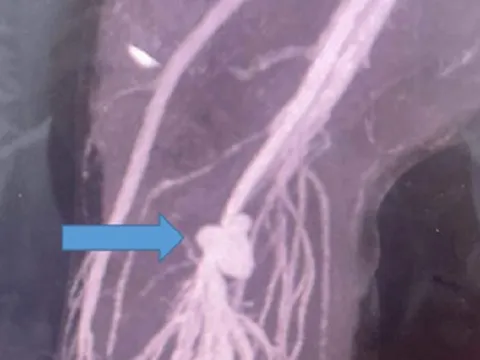

Nhồi máu cơ tim cấp sau khi đá bóng

Bệnh viện đa khoa tỉnh Thái Bình vừa điều trị thành công một bệnh nhân bị nhồi máu cơ tim cấp, tiền sử hoàn toàn khỏe mạnh và chưa có bệnh lý mạn...